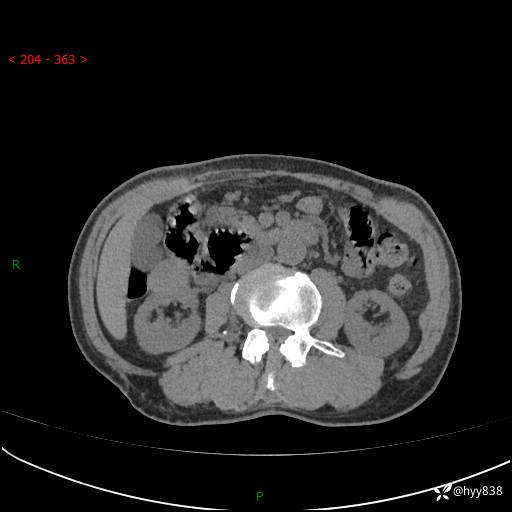

辅助检查:CT

临床诊断:肾肿物

肾脏CT平扫

增强(皮质期+髓质期+排泄期)

三期CT值:132hu 107hu 81hu